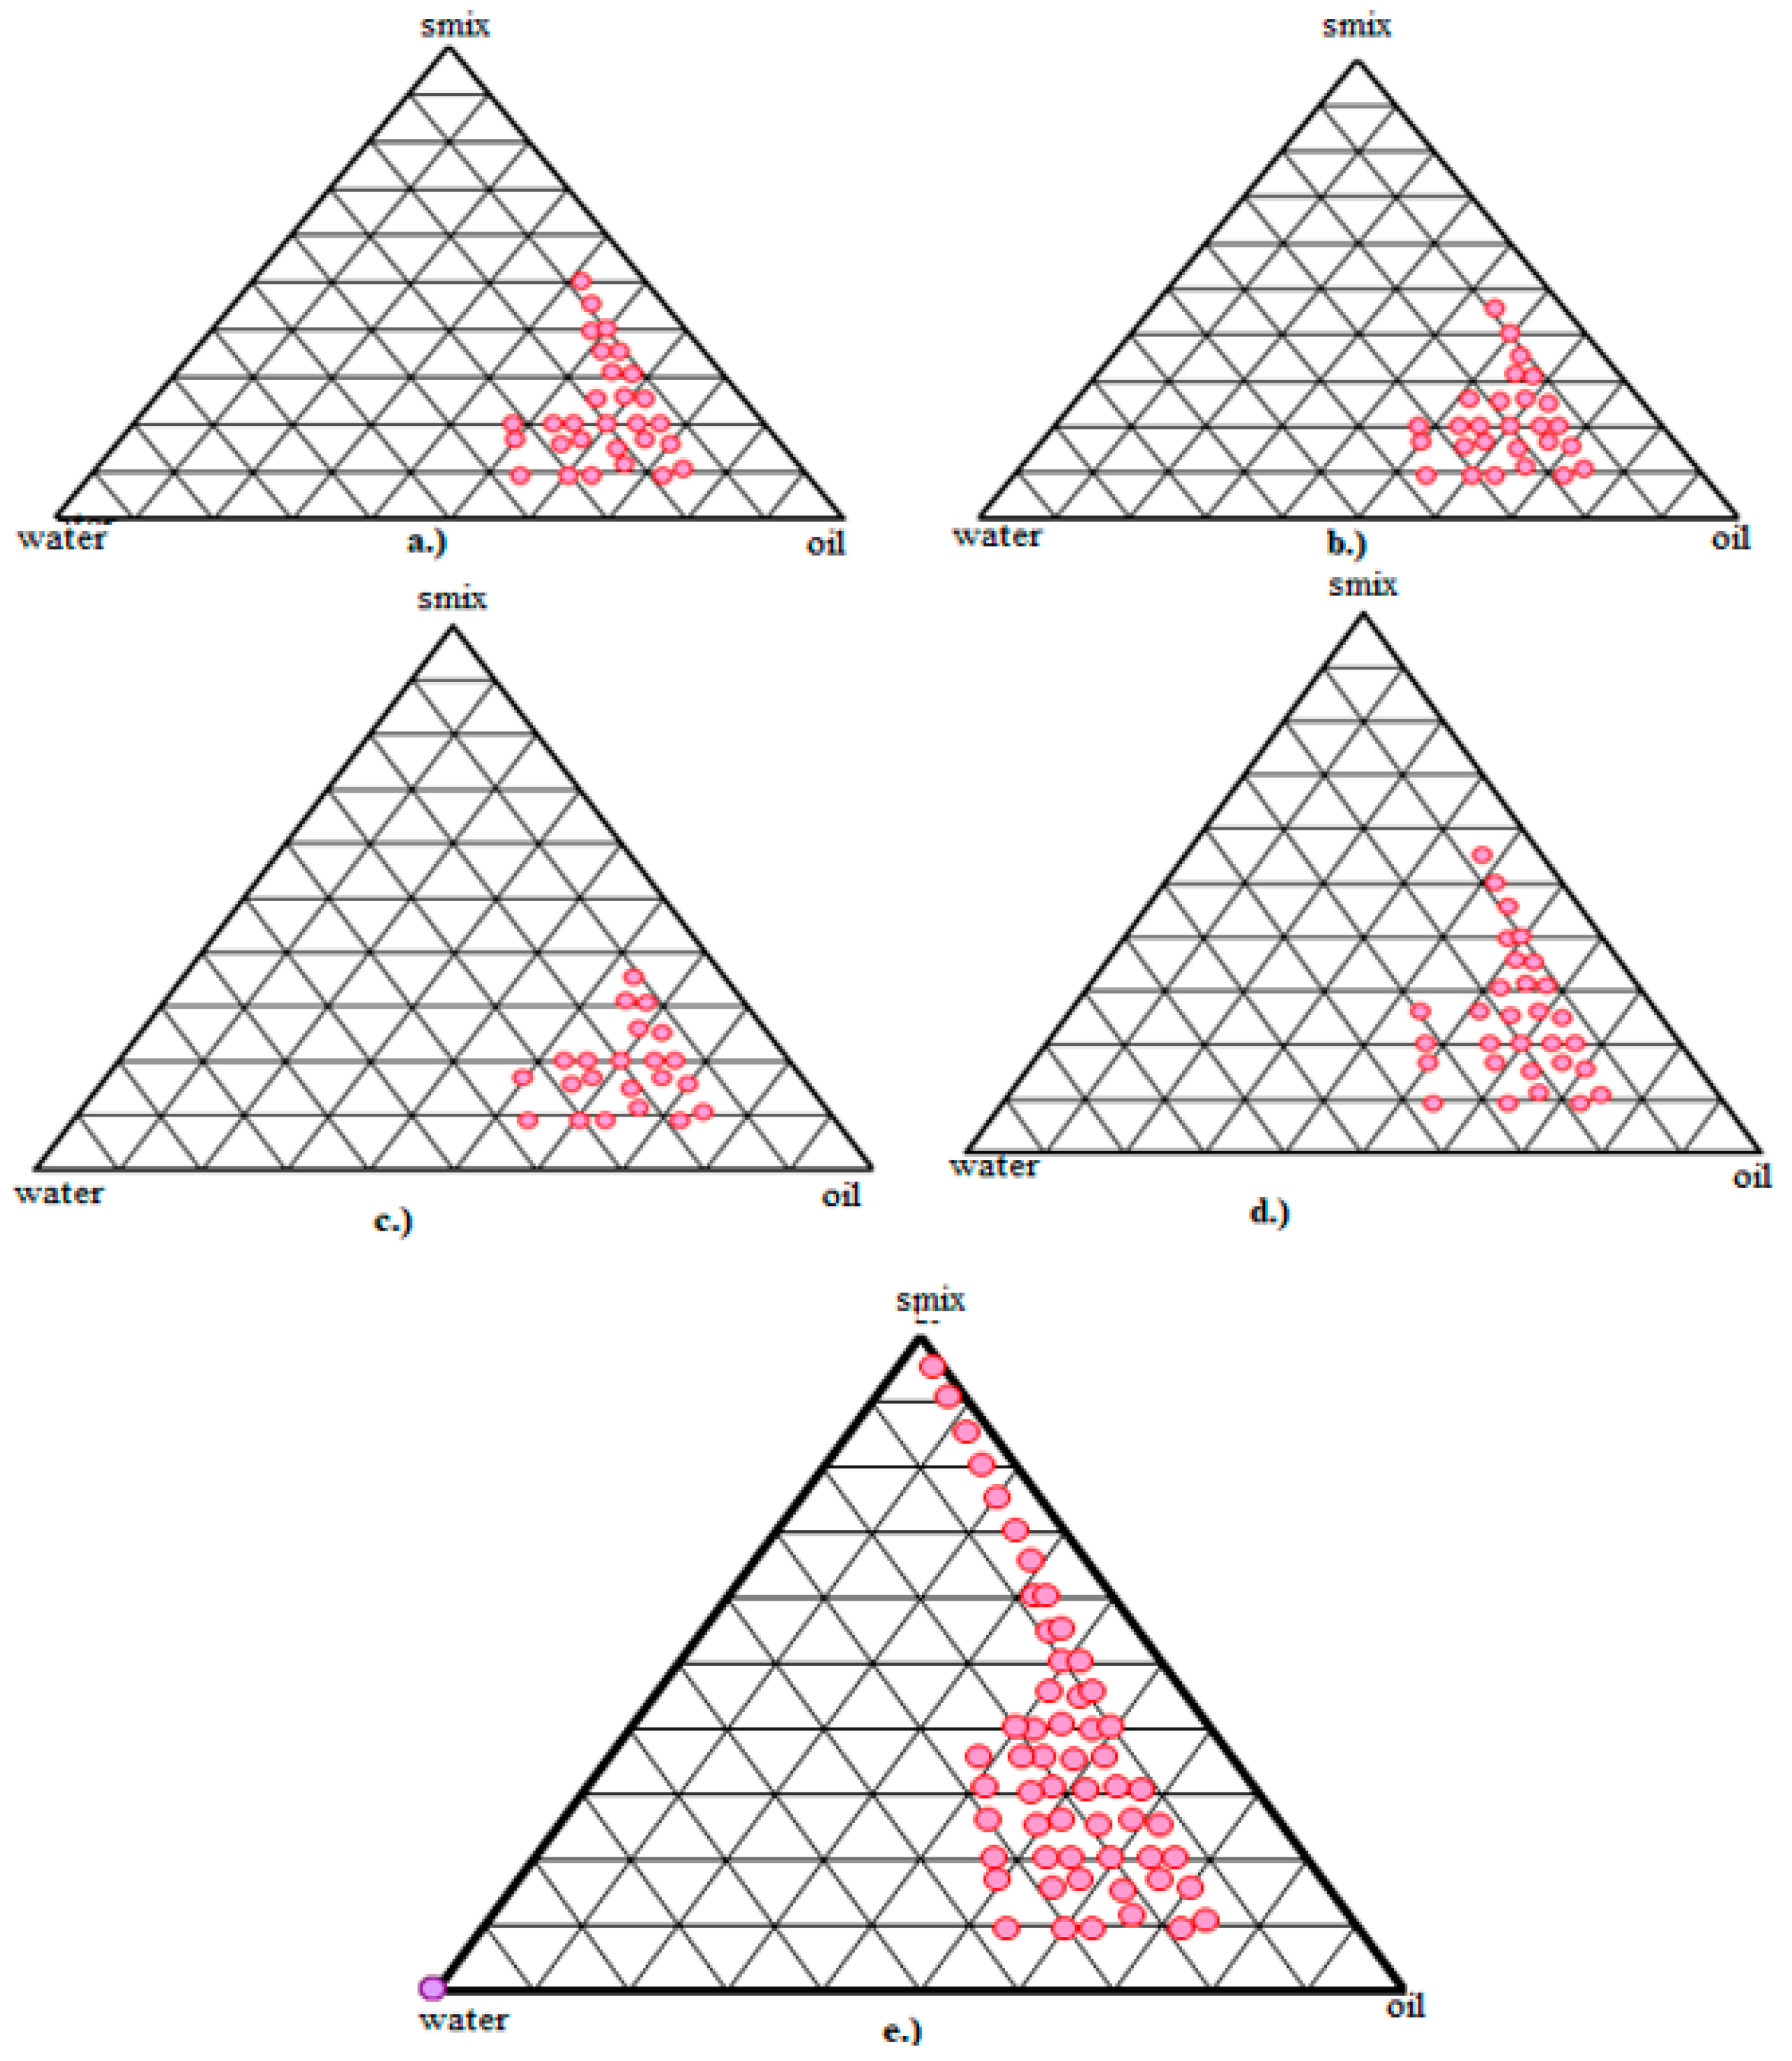

2.4. Pseudo-Ternary Phase Diagram Construction

3.4. Pseudo-Ternary Phase Diagram

3.5. Dispersion Stability Study